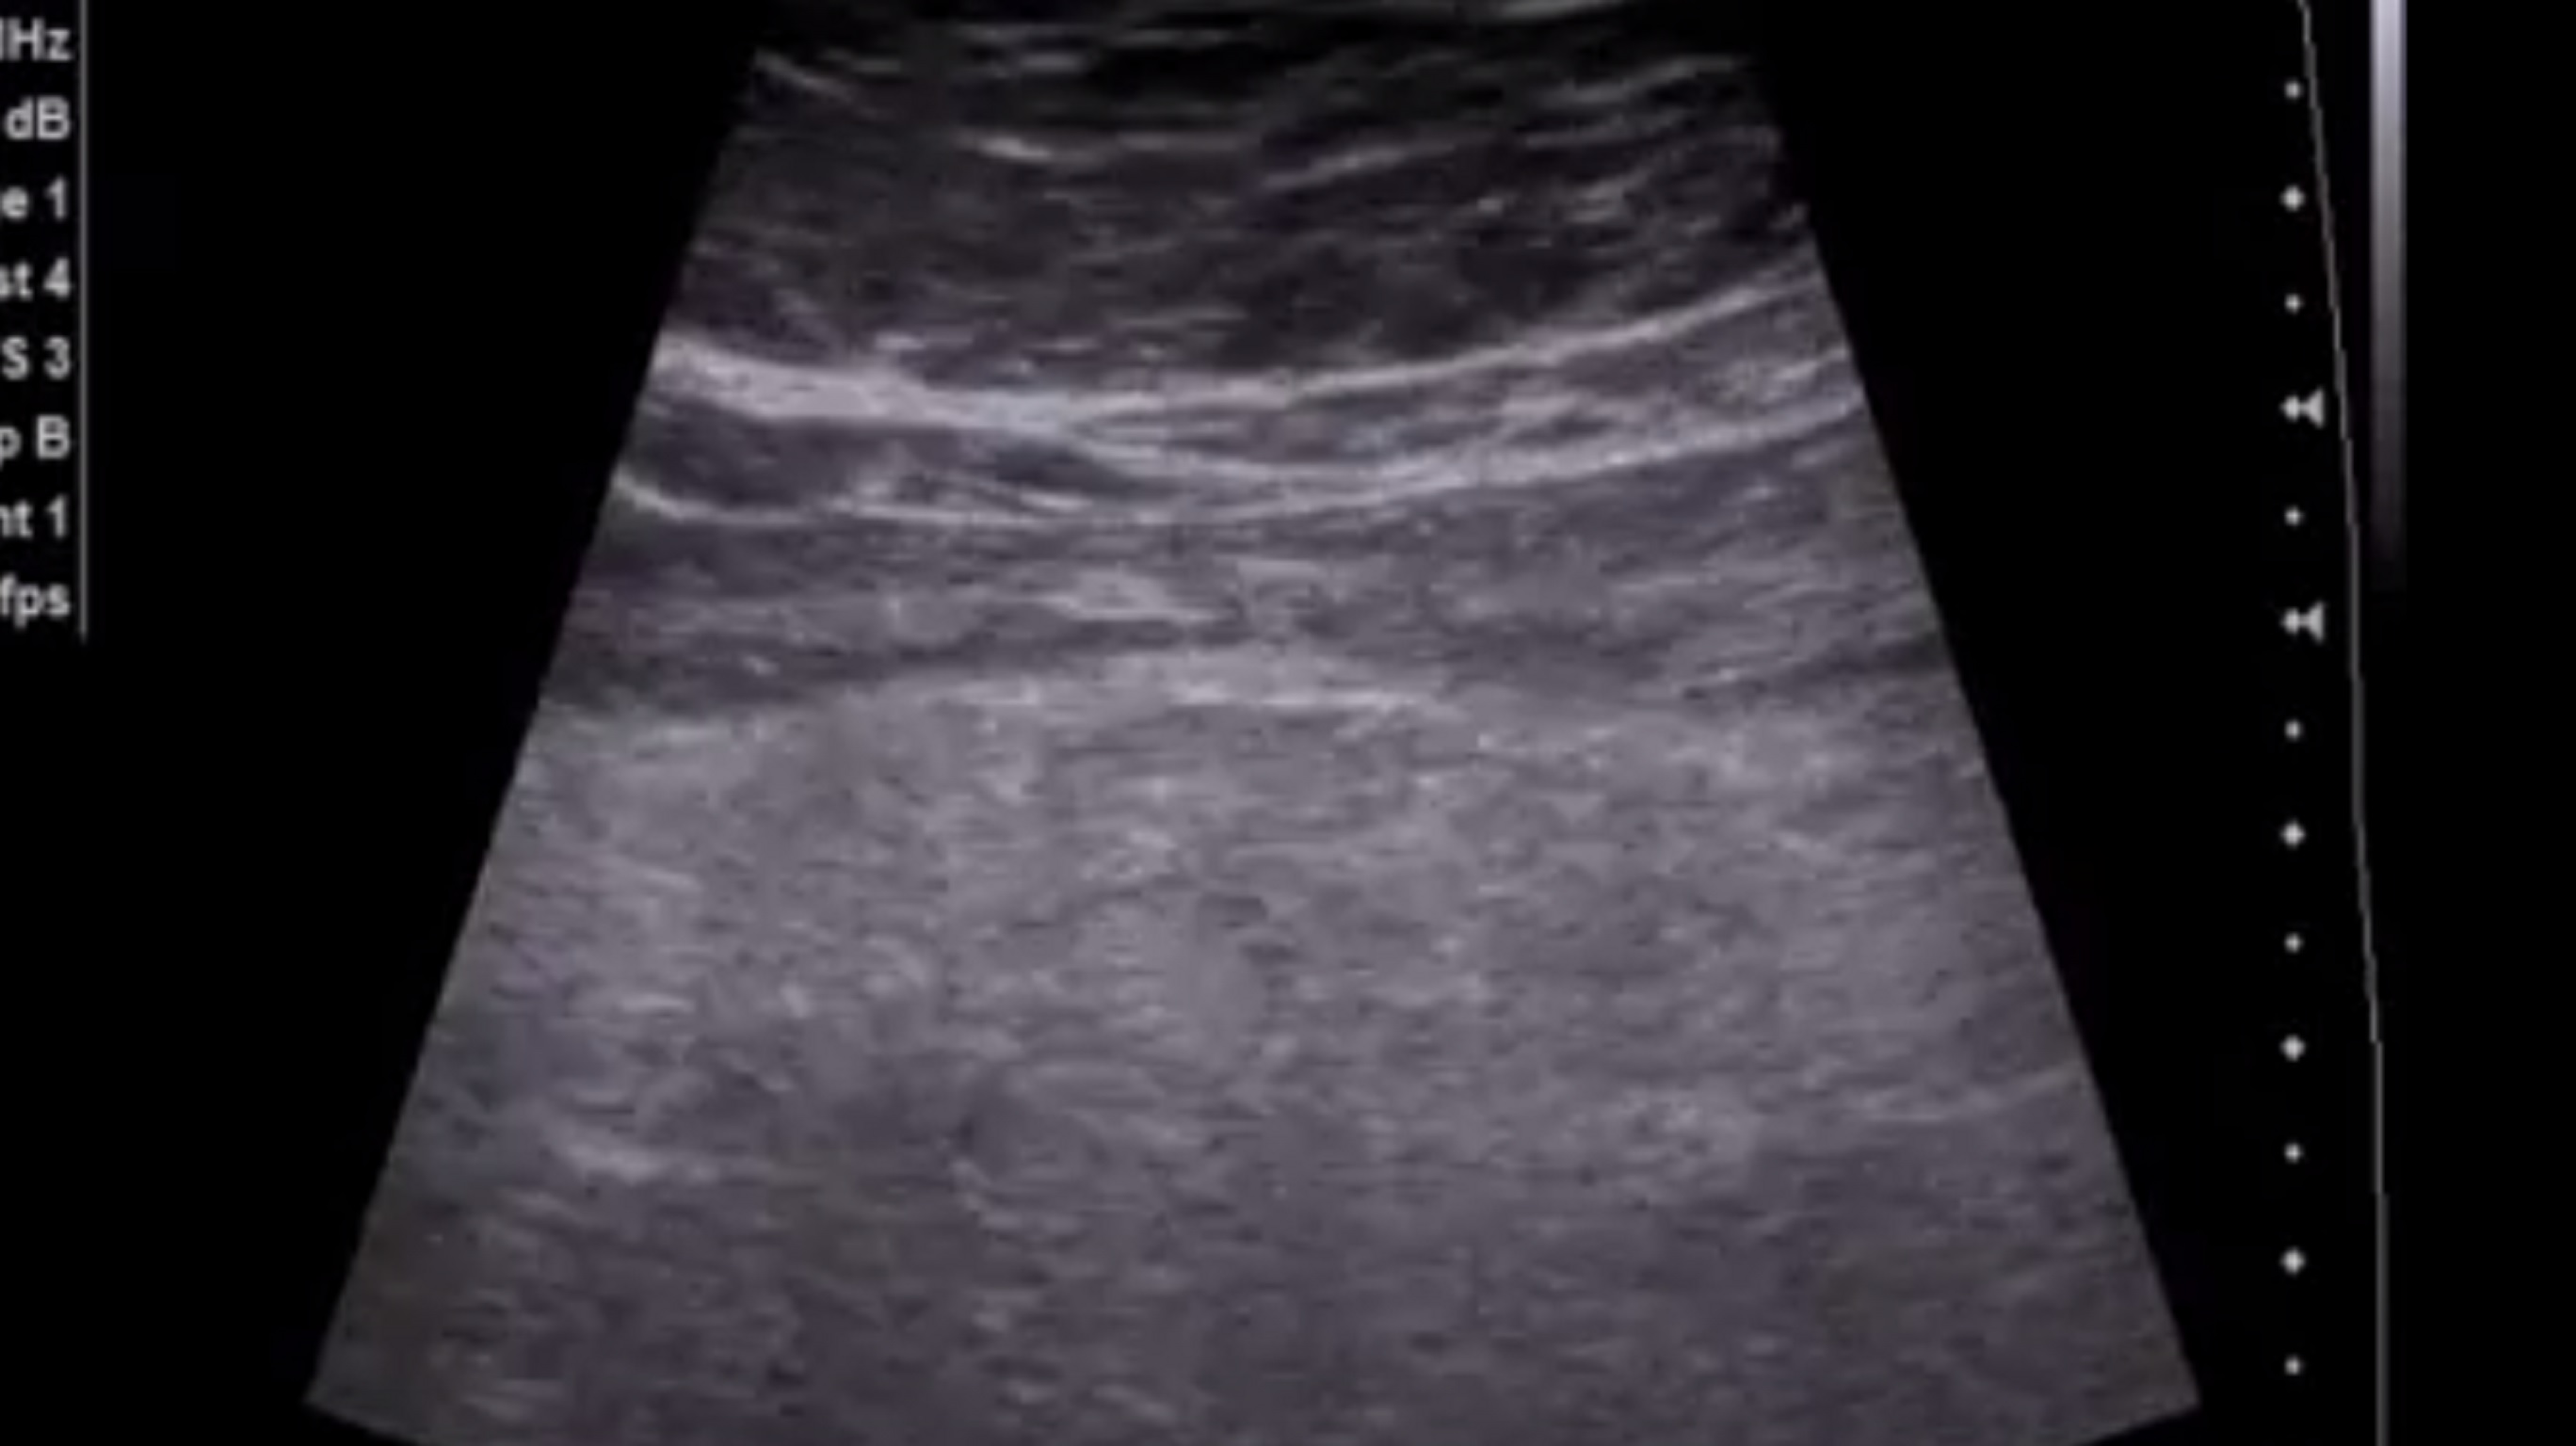

описание:

в проекции поперечно ободочной кишки, лоцируется фрагмент гиперэхогенного сальника , размером 12*4 см, с признаками кровотока на ЭДК

Заключение Уз признаки воспалительных изменений фрагмента большого сальника(инфаркт?)

посмотрите эхограммы, пожалуйста. В ролике можно сравнить эхогенность сальника в указанной области и правее